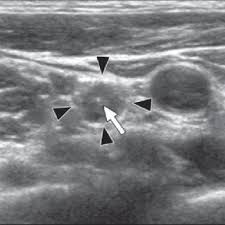

Enlarged Lymph Nodes In Head And Neck Cancer Analysis With Triplex Ultrasonography Sathyanarayan V Siva Bharani K Ann Maxillofac Surg from www.amsjournal.com Ultrasound an ultrasound is sometimes used, especially to look at the thyroid, salivary glands and lymph glands in the neck. Ultrasonography of neck lymph nodes; As thyroid cancer gets more advanced, you might notice symptoms like: Lumps can also form in the lips. A small lump on the neck usually is a lymph node, a small sebaceous cyst or a lipoma, although it could be something else. Reactive lymph nodes look different on ultrasound to lymphoma, so i'm sure the report to the gp will be the same as what she told you. Ultrasound is used to see the thyroid gland and the lymph node of the neck. During biopsy, the ultrasound helps make sure they are getting fna samples from the right areas.

Stage 4 Throat Cancer Life Expectancy Staging Types Risks from post.healthline.com For this scan, you will lie down and a gel will be spread over your neck. Two in three cases of thyroid cancer occur in people under age 55, and 75%. Ultrasound of the thyroid gland. A small lump on the neck usually is a lymph node, a small sebaceous cyst or a lipoma, although it could be something else. The doctor will also inspect the nose, mouth, throat, and tongue for abnormalities, often using a light and a mirror for a. 1 ), and the presence of an echogenic hilus within lymph nodes was previously considered a sign of benignity 44. Unfortunately cancer of the thyroid will not show up on an ultrasound. It is the same type of scan that is performed on pregnant women to view images of their unborn babies.

The sonographer stands facing the ultrasound and uses their right hand to move the transducer on the patient's neck, thus simultaneously facing both the ultrasound monitor ( on the left) and the patient's face ( on the right) figure 4.5. Are there signs of thyroid cancer on ultrasound? Sounds like they've been enlarged from an infection, maybe fighting one you weren't even aware of. A neck lump or nodule is the most common symptom of thyroid cancer. How a nodule looks on ultrasound can sometimes suggest if it is likely to be a cancer, but ultrasound can't tell for sure. Physical examination/blood and urine tests. Skin cancer is by far the most common type of cancer. An ultrasound of the neck is used to examine the carotid arteries located on each side of a patient's neck. The doctor will also inspect the nose, mouth, throat, and tongue for abnormalities, often using a light and a mirror for a. During a physical examination, the doctor feels for any lumps on the neck, lips, gums, and cheeks. Unfortunately cancer of the thyroid will not show up on an ultrasound. Most of the time, patients in the low risk group are simply monitored by ultrasound. An ultrasound scanner uses high frequency sound waves to create images of the internal soft tissues of the face and neck.

Non Thyroid Cystic Masses Identified On Neck Ultrasound from www.healio.com If you have a lump on it. During a physical examination, the doctor feels for any lumps on the neck, lips, gums, and cheeks. Air and bone also reflect sound waves. This means that they are larger than about 1 centimeter (about 1/2 inch) across. A neck ultrasound can be used to observe the thyroid gland to look for nodules, growths, or tumors. Epidemiology it typically presents in younger women with an average age of onset at around 45 y. Ultrasounds are usually quick and most don't require special preparation. The sonographer stands facing the ultrasound and uses their right hand to move the transducer on the patient's neck, thus simultaneously facing both the ultrasound monitor ( on the left) and the patient's face ( on the right) figure 4.5.

Doctors often use them to guide a needle during a biopsy. Carotid ultrasound tests for blocked or narrowed carotid arteries, which can increase the. If left unchecked, the cancer can break out of the lymph node and spread to the surrounding. This picture gallery contains some examples of the more common. Ultrasound is relatively quick and simple test that gives very useful information about the soft tissues in the head and neck region including the lymph. Thyroid nodules, or lumps, are very common.most aren't cancer. Reactive lymph nodes look different on ultrasound to lymphoma, so i'm sure the report to the gp will be the same as what she told you. Trusted, accurate neck ultrasound, from the experts in anchorage. The doctor will also inspect the nose, mouth, throat, and tongue for abnormalities, often using a light and a mirror for a. Epidemiology it typically presents in younger women with an average age of onset at around 45 y. Malignant cyst look more complex and may have solid areas. Doctors in 147 specialties are here to answer your questions or offer you advice, prescriptions, and more. Two in three cases of thyroid cancer occur in people under age 55, and 75%.